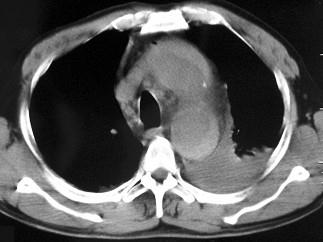

问题 男,58岁,有高血压病史,突发胸背剧痛,CT扫描如图,其最可能的诊断为 ( )

选项 A、高安氏病 B、主动脉夹层动脉瘤 C、主动脉假性动脉瘤 D、主动脉窦瘤破裂 E、主动脉瘤

答案 B